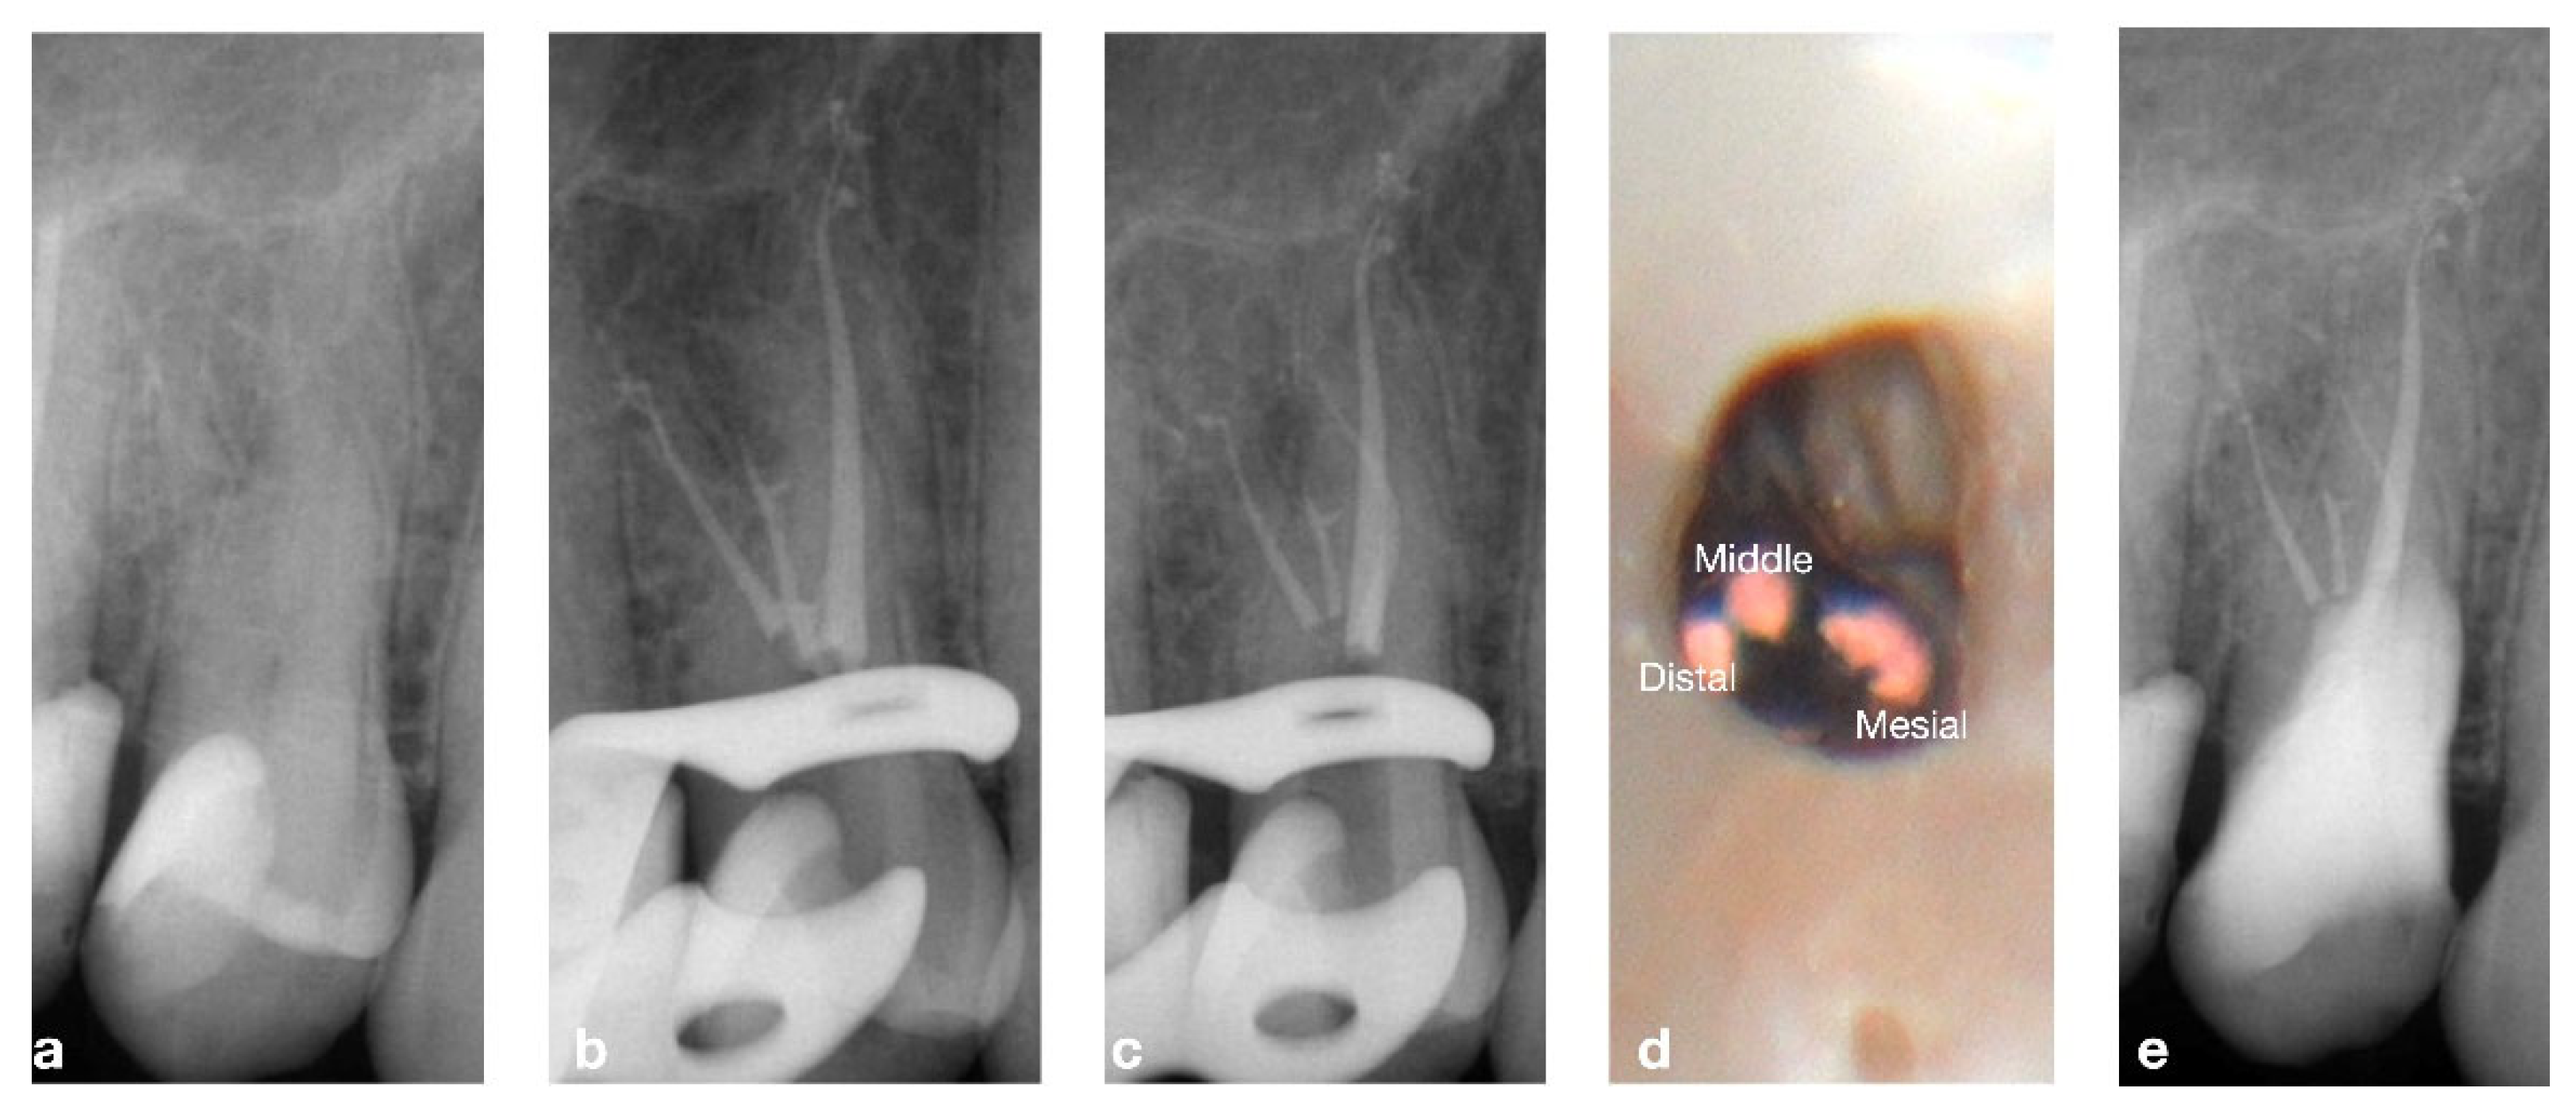

2.1. CASE 1